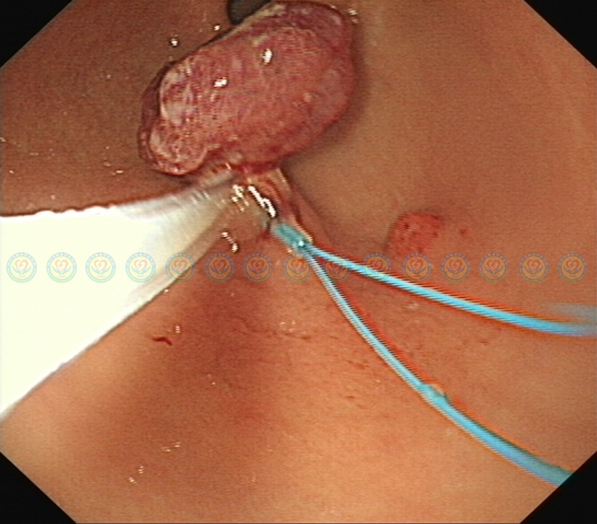

内镜下送入尼龙圈结扎器,结扎肿块蒂部。

结扎后肿块变色、变小,提示结扎有效。